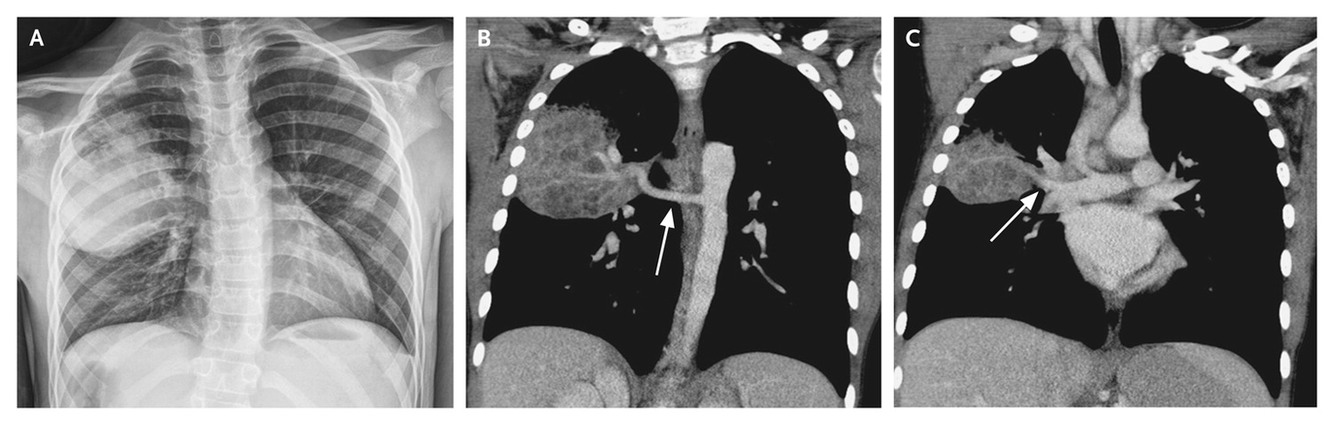

Scimitar syndrome is

Hypoplastic right lung and anomalous right pulmonary venous connection to IVC. AKA hypogenetic lung syndrome or congenital pulmonary venolobar syndrome.

Often anomalous systemic arterial supply to the right lung.